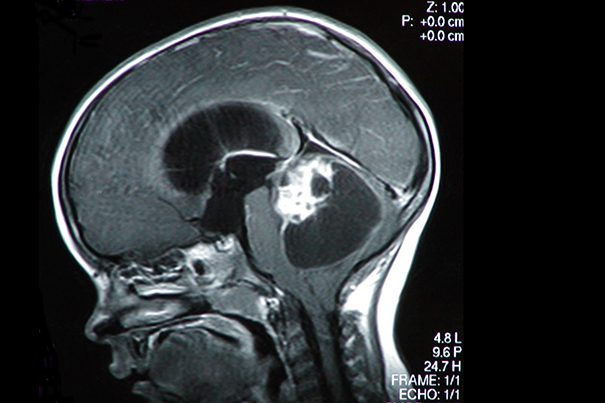

• Harnessing nature to beat cancer

Every year, more than 18 million people around the world are told, “You have cancer.” In the U.S., nearly half of all men and more than one-third of women will…

Nanoparticles